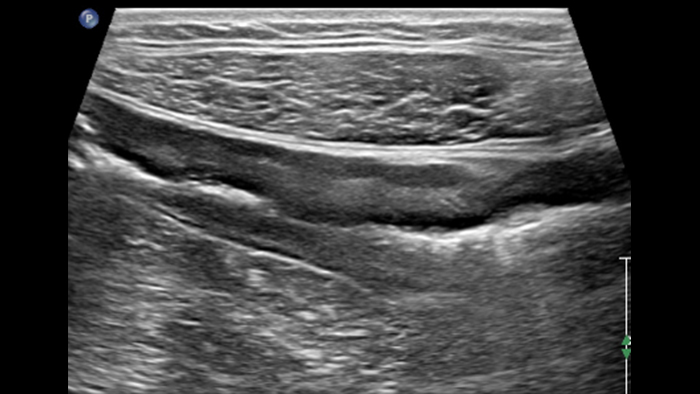

Ces images précises des lésions des couches pariétales forment la base de l’interprétation des changements induits par l’inflammation des parois intestinales et par conséquent de la différenciation entre la maladie de Crohn et la rectocolite hémorragique. L’exploration avec la technologie MFI (MicroFlow Imaging) constitue la deuxième étape. Il s’agit de reconnaître l’aspect de l’hypervascularisation induite par des épisodes inflammatoires actifs. La paroi intestinale normale semble comporter peu de microvaisseaux détectables, uniquement à l’interface de la muqueuse et de la sous-muqueuse, et dans le tissu adipeux mésentérique adjacent. Inversement, la paroi inflammatoire présente de nombreux microvaisseaux. La distinction entre les images d’artefacts de mouvement et les microvaisseaux circulants est alors un point essentiel nécessitant un ajustement parfait des paramètres de détection des micro-flux (voir les boucles, diapositive 8). La comparaison des 4 images suivantes de la maladie de Crohn met en évidence des différences claires qui devraient être interprétées comme étant représentatives des différents états inflammatoires. L’image 1 ne comporte aucun vaisseau visible, ce qui correspond probablement à une absence d’activité. L’image 2 présente quelques vaisseaux ; nous pouvons en conclure que cela correspond à une activité modérée. L’image 3 comporte un plus grand nombre de vaisseaux, signe probable d’une activité intense. L’image 4 présente encore plus de vaisseaux de type pulsatile, ce qui évoque probablement une activité très intense.

Numerous vessels severe activity ?